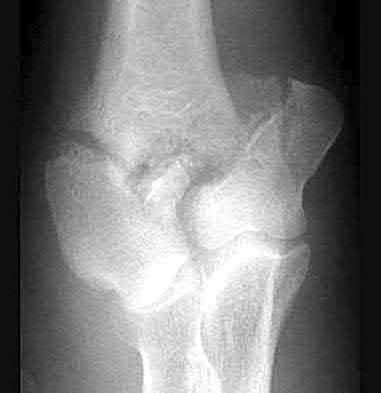

1012) A 54-year-old woman sustains the injury seen in Figures 71a and 71b. The injury involves her nondominant extremity. What should the patient be told regarding her expected outcome?

Corrent answer: 3

This is a Bado type 2 (posterior) Monteggia lesion, which is associated with higher rates of complications than other types of Monteggia lesions. The injury is associated with indirect high-energy trauma and less often pathologic causes. Of the four types of Monteggia lesions, the type 2 or posterior type is associated with the worst prognosis. These injuries are best treated surgically with dorsal plating of the ulna and reduction with fixation or arthroplasty of the radial head. The major complications seen with this injury pattern are nonunion and plate failure. Almost all patients have some loss of elbow range of motion. Satisfactory results based on functional scores for this injury are not universal. Neurologic injury and ulnohumeral instability are unusual with this type of injury. Full functional recovery is not expected with nonsurgical management.